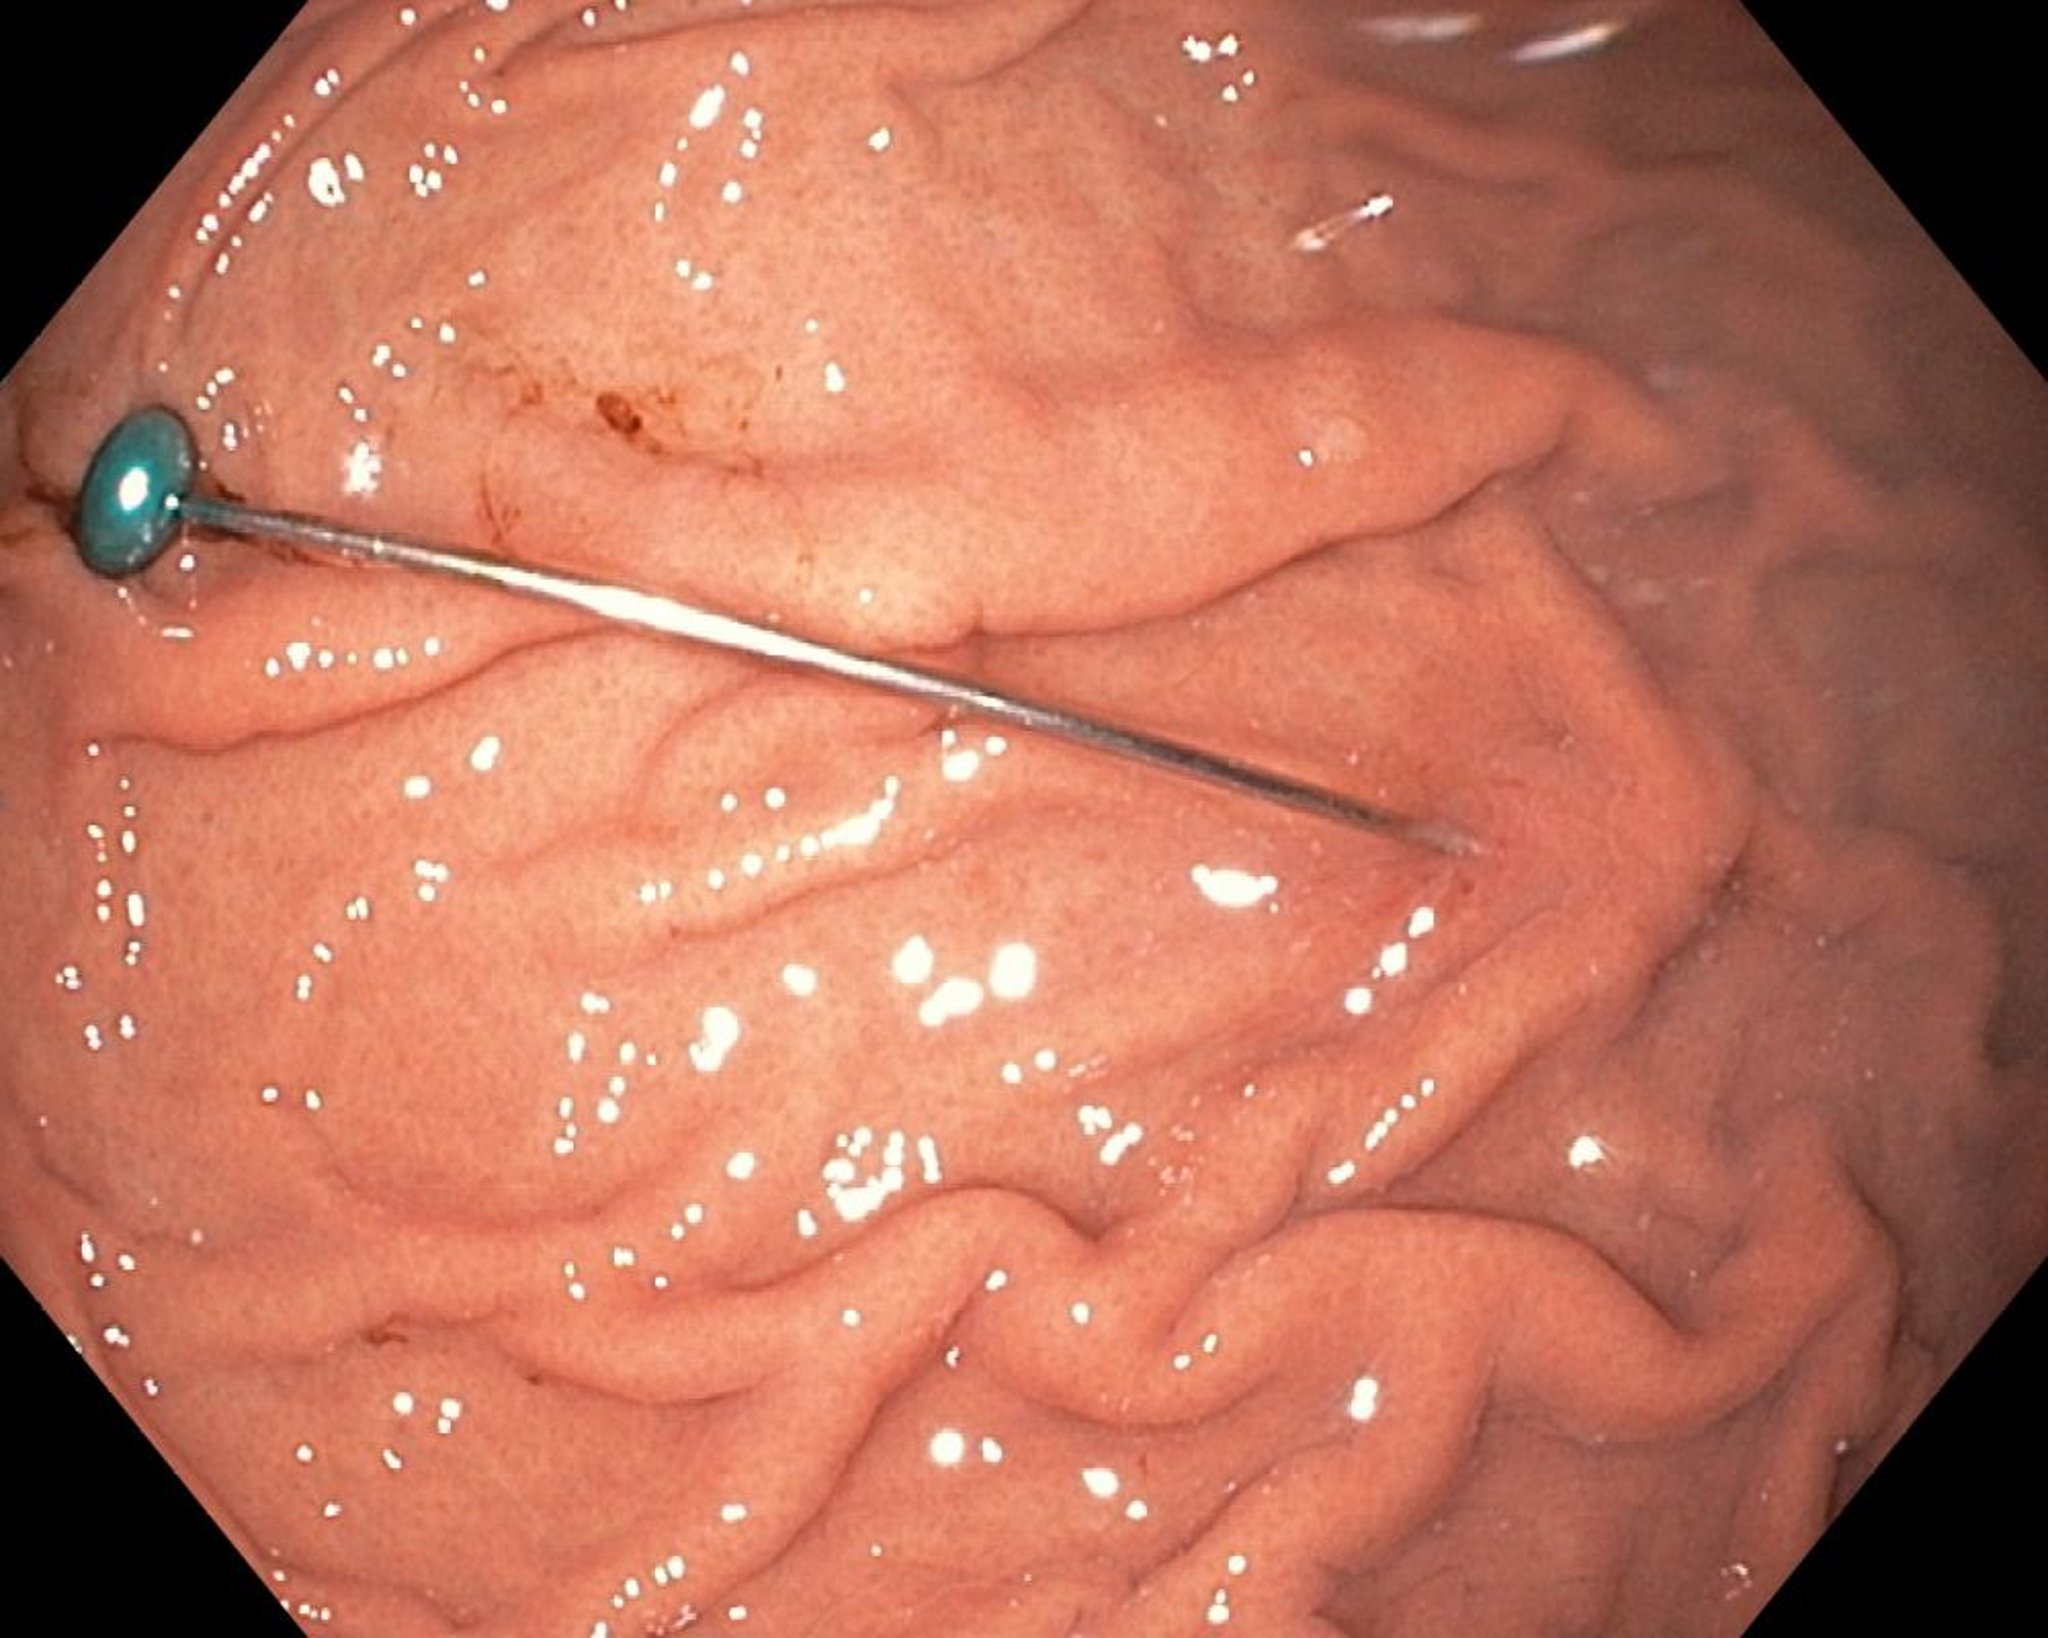

Чужорідне тіло в шлунку (ендоскопія)

This endoscopic image shows a sharp foreign body in the stomach.

Image provided by Uday Shankar, MD.